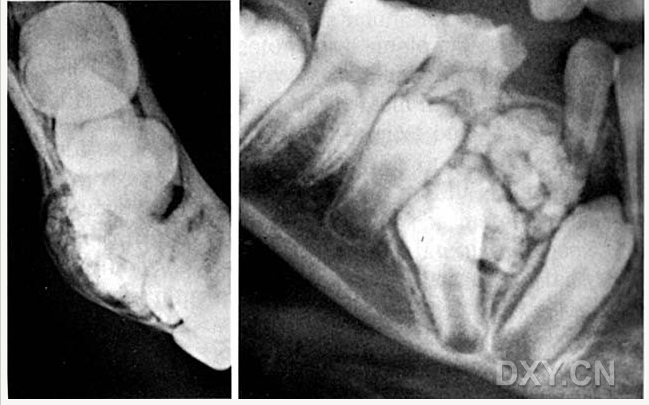

含牙囊腫

牙源性鈣化囊腫

牙瘤!

牙源性鈣化囊腫    牙瘤!

牙瘤